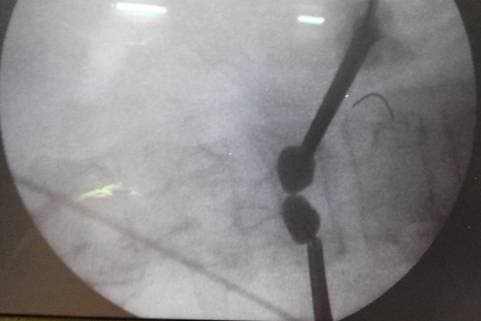

Состояние после удаления баллонов и введения цемента

Костный цемент (чёрным цветом) заполняет полость после удаления баллонов